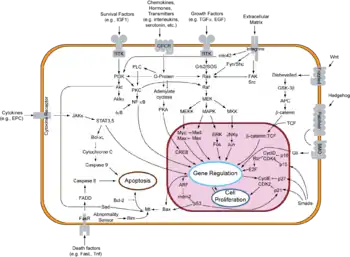

Cancer cells have defects in the control mechanisms that govern how often they divide, and in the feedback systems that regulate these control mechanisms (i.e. defects in homeostasis).

Normal cells grow and divide, but have many controls on that growth. They only grow when stimulated by growth factors. If they are damaged, a molecular brake stops them from dividing until they are repaired. If they can't be repaired, they commit programmed cell death (apoptosis). They can only divide a limited number of times. They are part of a tissue structure, and remain where they belong. They need a blood supply to grow.

All these mechanisms must be overcome in order for a cell to develop into a cancer. Each mechanism is controlled by several proteins. A critical protein must malfunction in each of those mechanisms. These proteins become non-functional or malfunctioning when the DNA sequence of their genes is damaged through acquired or somatic mutations (mutations that are not inherited but occur after conception). This occurs in a series of steps, which Hanahan and Weinberg refer to as hallmarks.

Typically, cells of the body require hormones and other molecules that act as signals for them to grow and divide. Cancer cells, however, have the ability to grow without these external signals. There are multiple ways in which cancer cells can do this: by producing these signals themselves, known as autocrine signalling; by permanently activating the signalling pathways that respond to these signals; or by destroying 'off switches' that prevents excessive growth from these signals (negative feedback). In addition, cell division in normal, non-cancerous cells is tightly controlled. In cancer cells, these processes are deregulated because the proteins that control them are altered, leading to increased growth and cell division within the tumor.[4][5]

To tightly control cell division, cells have processes within them that prevent cell growth and division. These processes are orchestrated by proteins known as tumor suppressor genes. These genes take information from the cell to ensure that it is ready to divide, and will halt division if not (when the DNA is damaged, for example). In cancer, these tumour suppressor proteins are altered so that they don't effectively prevent cell division, even when the cell has severe abnormalities. Another way cells prevent over-division is that normal cells will also stop dividing when the cells fill up the space they are in and touch other cells; known as contact inhibition. Cancer cells do not have contact inhibition, and so will continue to grow and divide, regardless of their surroundings.[4][6]

Cells have the ability to 'self-destruct'; a process known as apoptosis. This is required for organisms to grow and develop properly, for maintaining tissues of the body, and is also initiated when a cell is damaged or infected. Cancer cells, however, lose this ability; even though cells may become grossly abnormal, they do not undergo apoptosis. The cancer cells may do this by altering the mechanisms that detect the damage or abnormalities. This means that proper signaling cannot occur, thus apoptosis cannot activate. They may also have defects in the downstream signaling itself, or the proteins involved in apoptosis, each of which will also prevent proper apoptosis.[4][7]

Cells of the body don't normally have the ability to divide indefinitely. They have a limited number of divisions before the cells become unable to divide (senescence), or die (crisis). The cause of these barriers is primarily due to the DNA at the end of chromosomes, known as telomeres. Telomeric DNA shortens with every cell division, until it becomes so short it activates senescence, so the cell stops dividing. Cancer cells bypass this barrier by manipulating enzymes (telomerase) to increase the length of telomeres. Thus, they can divide indefinitely, without initiating senescence.[4][8]

Normal tissues of the body have blood vessels running through them that deliver oxygen from the lungs. Cells must be close to the blood vessels to get enough oxygen for them to survive. New blood vessels are formed during the development of embryos, during wound repair and during the female reproductive cycle. An expanding tumour requires new blood vessels to deliver adequate oxygen to the cancer cells, and thus exploits these normal physiological processes for its benefit. To do this, the cancer cells acquire the ability to orchestrate production of new vasculature by activating the 'angiogenic switch'. In doing so, they control non-cancerous cells that are present in the tumor that can form blood vessels by reducing the production of factors that inhibit blood vessel production, and increasing the production of factors that promote blood vessel formation.[4][10]

One of the most well known properties of cancer cells is their ability to invade neighboring tissues. It is what dictates whether the tumor is benign or malignant, and is the property which enables their dissemination around the body. The cancer cells have to undergo a multitude of changes in order for them to acquire the ability to metastasize, in a multistep process that starts with local invasion of the cells into the surrounding tissues. They then have to invade blood vessels, survive in the harsh environment of the circulatory system, exit this system and then start dividing in the new tissue.[4][11]

Most cancer cells use alternative metabolic pathways to generate energy, a fact appreciated since the early twentieth century with the postulation of the Warburg hypothesis,[12][13] but only now gaining renewed research interest.[14] Cancer cells exhibiting the Warburg effect upregulate glycolysis and lactic acid fermentation in the cytosol and prevent mitochondria from completing normal aerobic respiration (oxidation of pyruvate, the citric acid cycle, and the electron transport chain). Instead of completely oxidizing glucose to produce as much ATP as possible, cancer cells would rather convert pyruvate into the building blocks for more cells. In fact, the low ATP:ADP ratio caused by this effect likely contributes to the deactivation of mitochondria. Mitochondrial membrane potential is hyperpolarized to prevent voltage-sensitive permeability transition pores (PTP) from triggering of apoptosis.[15][16]

Despite cancer cells causing increased inflammation and angiogenesis, they also appear to be able to avoid interaction with the body's immune system via a loss of interleukin-33. (See cancer immunology)